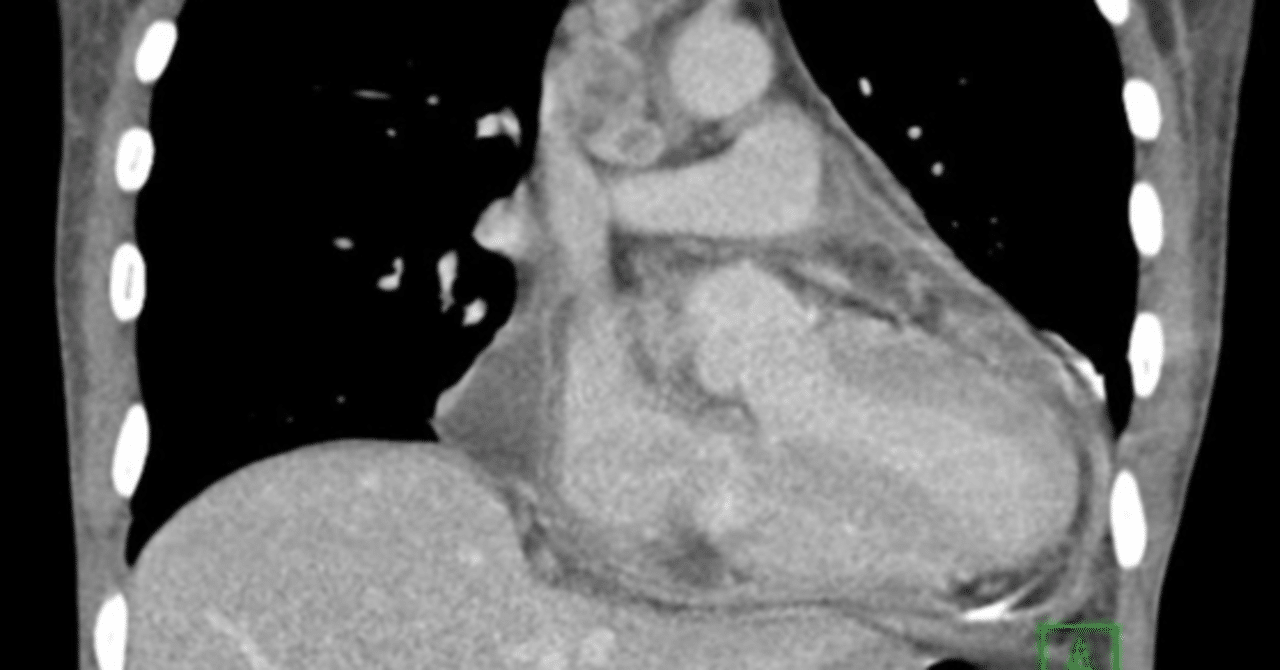

心嚢液貯留

心膜液貯留は、心膜と心臓の間に過剰な液体が蓄積することです。これは心膜の損傷や病気によって発生する可能性があります。損傷後に心膜内に出血がある場合にも体液が蓄積する可能性があります。

心タンポナーデ

心タンポナーデは、心膜腔内の体液、血液、ガス、または腫瘍の蓄積によって引き起こされる状態です。この蓄積により心臓に圧力がかかり、心臓が適切に満たされたり排出されたりすることができなくなります。

心タンポナーデは心嚢液貯留と同じではありませんが、心嚢液貯留による体液の蓄積の合併症である可能性があります。

心タンポナーデの兆候の 1 つは、血圧の大幅な低下です。心タンポナーデは医療上の緊急事態です。すぐに治療しないと命に関わる可能性があります。